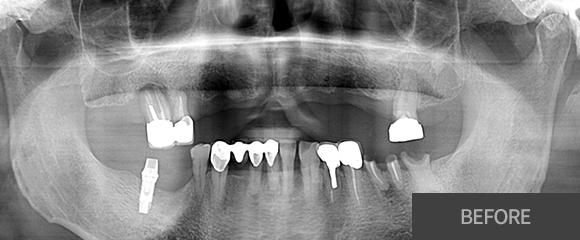

전악(전체) 임플란트

CASE 1